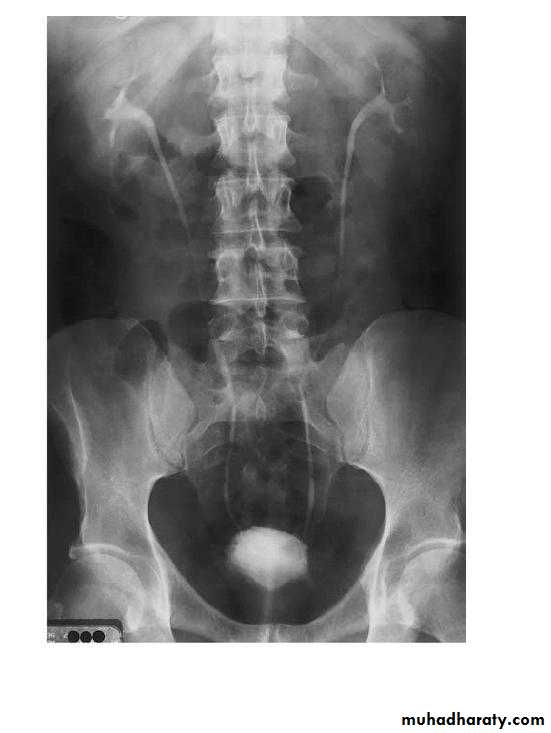

Normal IVU

nephrogram

pyelogram